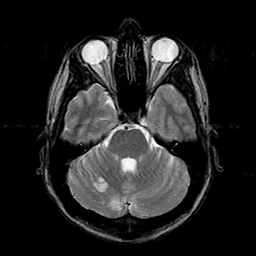

Sarcoma, MR Study #1 mr-t2 -- Slice #6

[Home][Help][Clinical] Slice 6